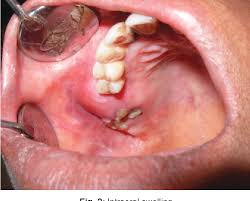

What Does Bone Cancer In The Mouth Look Like - Jaw Cancer Signs Symptoms Causes Diagnosis And Treatment / This can lead to insomnia, loss of appetite, and inability to carry out normal daily activities.. What bone metastasis looks like. Some of the most common oral cancer symptoms and signs include: Inner cheek cancer (also called buccal mucosa cancer) is a type of head and neck cancer that begins when the cells that make up the inner cheek grow out of control and form lesions or tumors. Patches on the lining of the mouth or tongue, usually red or red and white bleeding, pain, or numbness in the mouth mouth ulcers or sores that do not heal Taken by mouth or injection, they attack any cancer cells in the body.

Jaw cancer results in pain in the area with difficulty in opening the mouth. As you review these images and their descriptions, you. Usually it's spotted first by your dentist, so keeping regular dental exams can help with early detection. What bone metastasis looks like. It will show the normal anatomy of the bone and the additional growth arising from the bone and we can see the exact dimensions of the cancer and its local extent of spread and invasion into the surrounding tissues. With time they may spread inside the mouth and on to other areas of the head and neck or other parts of the body. Early on, the pain may only occur at night, or when you are active. Each tumor looks like it's the original site of disease on the scans, suggesting that the bone tumors developed independently, at the same time, at multiple sites. This can lead to insomnia, loss of appetite, and inability to carry out normal daily activities. At first the ulcer is painless, but it later becomes painful. People with a fracture next to or through a bone tumor usually describe sudden severe pain in a bone that had been sore for a few months. Tongue cancer is a type of cancer that starts in the cells of the tongue, and can cause lesions or tumors on your tongue. Cancer in the bones of the spine can press on nerves, causing numbness and tingling or even.

Each tumor looks like it's the original site of disease on the scans, suggesting that the bone tumors developed independently, at the same time, at multiple sites. It is a good imaging: At first the ulcer is painless, but it later becomes painful. Buccal mucosa is another name for the inside lining of the cheeks. The appearance of feline oral cancer can vary significantly, depending on the type of cancer and how far advanced the cancer is.

Metastatic Tumors To The Jaws A Report Of Eight New Cases from scielo.isciii.es Some of the most common oral cancer symptoms and signs include: Chemotherapy, hormone therapy, and immunotherapy target the main cancer. Other conditions, like osteoporosis or arthritis, may also cause bone or joint pain. Malignant cells in the jaw tend to spread quickly to adjacent organs. The sore may be red or white and may look like a thickening of the gum. At first the ulcer is painless, but it later becomes painful. Soft palate cancer starts in the soft palate cells, which are on the upper portion of the back of your mouth, right behind your teeth. The ulcer may bleed as the cancer grows.